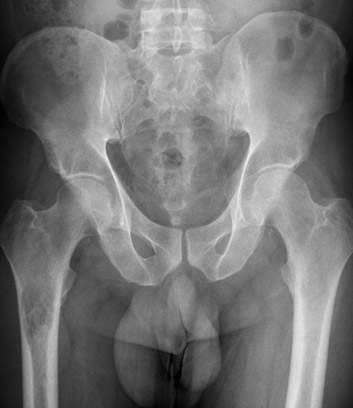

Carcinoma medular renal.

El carcinoma medular renal es una variedad de tumor renal muy infrecuente, diagnosticándose en fase avanzada metastásica y presentando un pronóstico nefasto a corto plazo. No existen directrices claras acerca de su manejo por la escasa evidencia sobre esta entidad. Presentamos un caso de un paciente afecto de carcinoma medular renal.